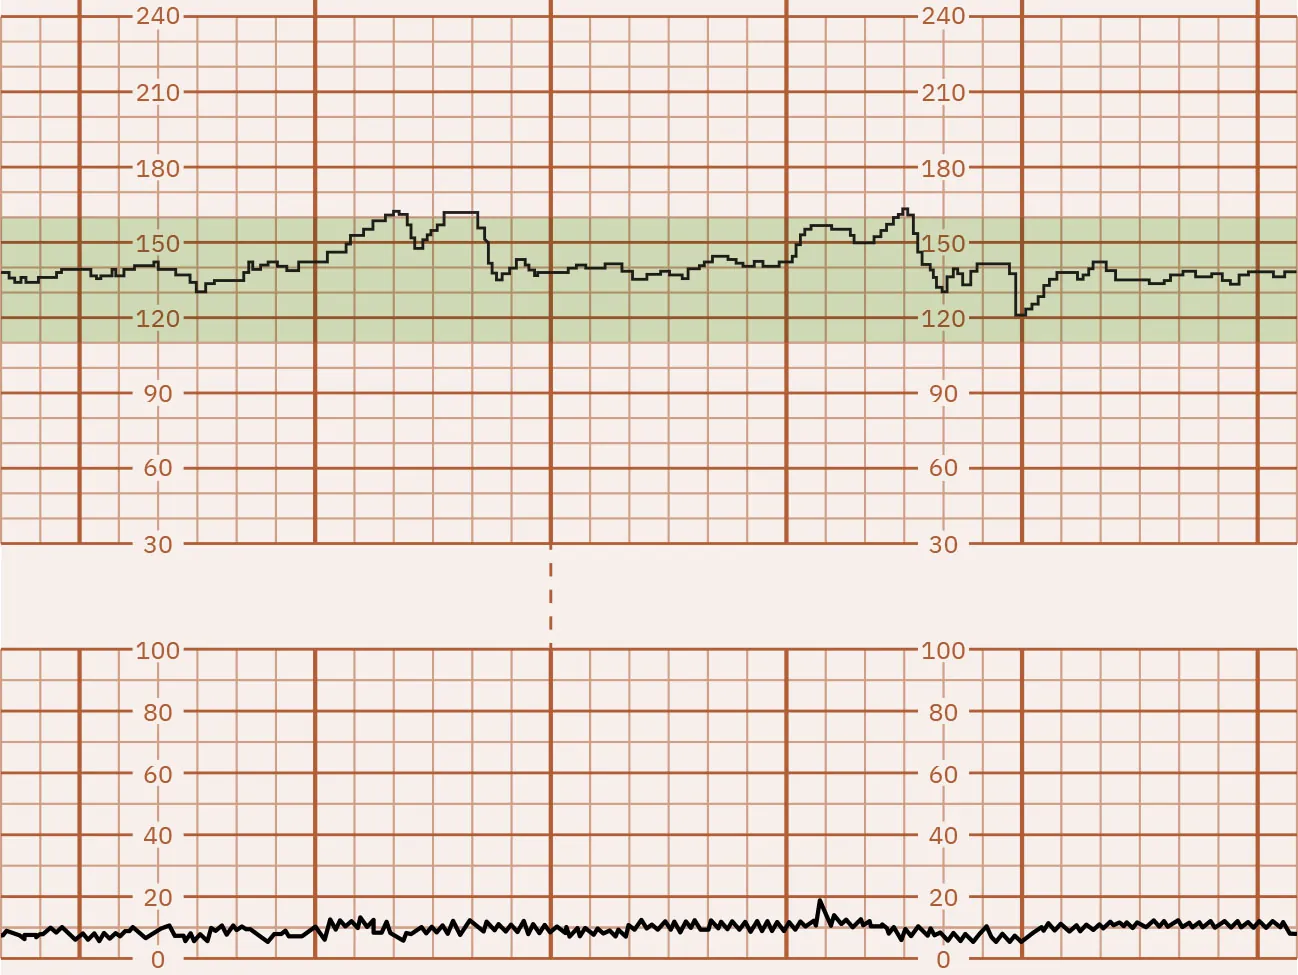

Moderate FHR Variability

Fluctuations between 6 and 25 bpm are considered moderate FHR variability. This is considered normal FHR variability. In most cases, moderate FHR variability is associated with a normal umbilical cord pH. Figure 16.5 shows a monitor tracing that indicates moderate FHR variability.

Fetal heart rate reading indicating moderate variability.

Figure 16.5 Fetal Monitor Tracing: Moderate FHR Variability This fetal monitor tracing shows moderate variability of 6 to 25 bpm. (attribution: Copyright Rice University, OpenStax, under CC BY 4.0 license)